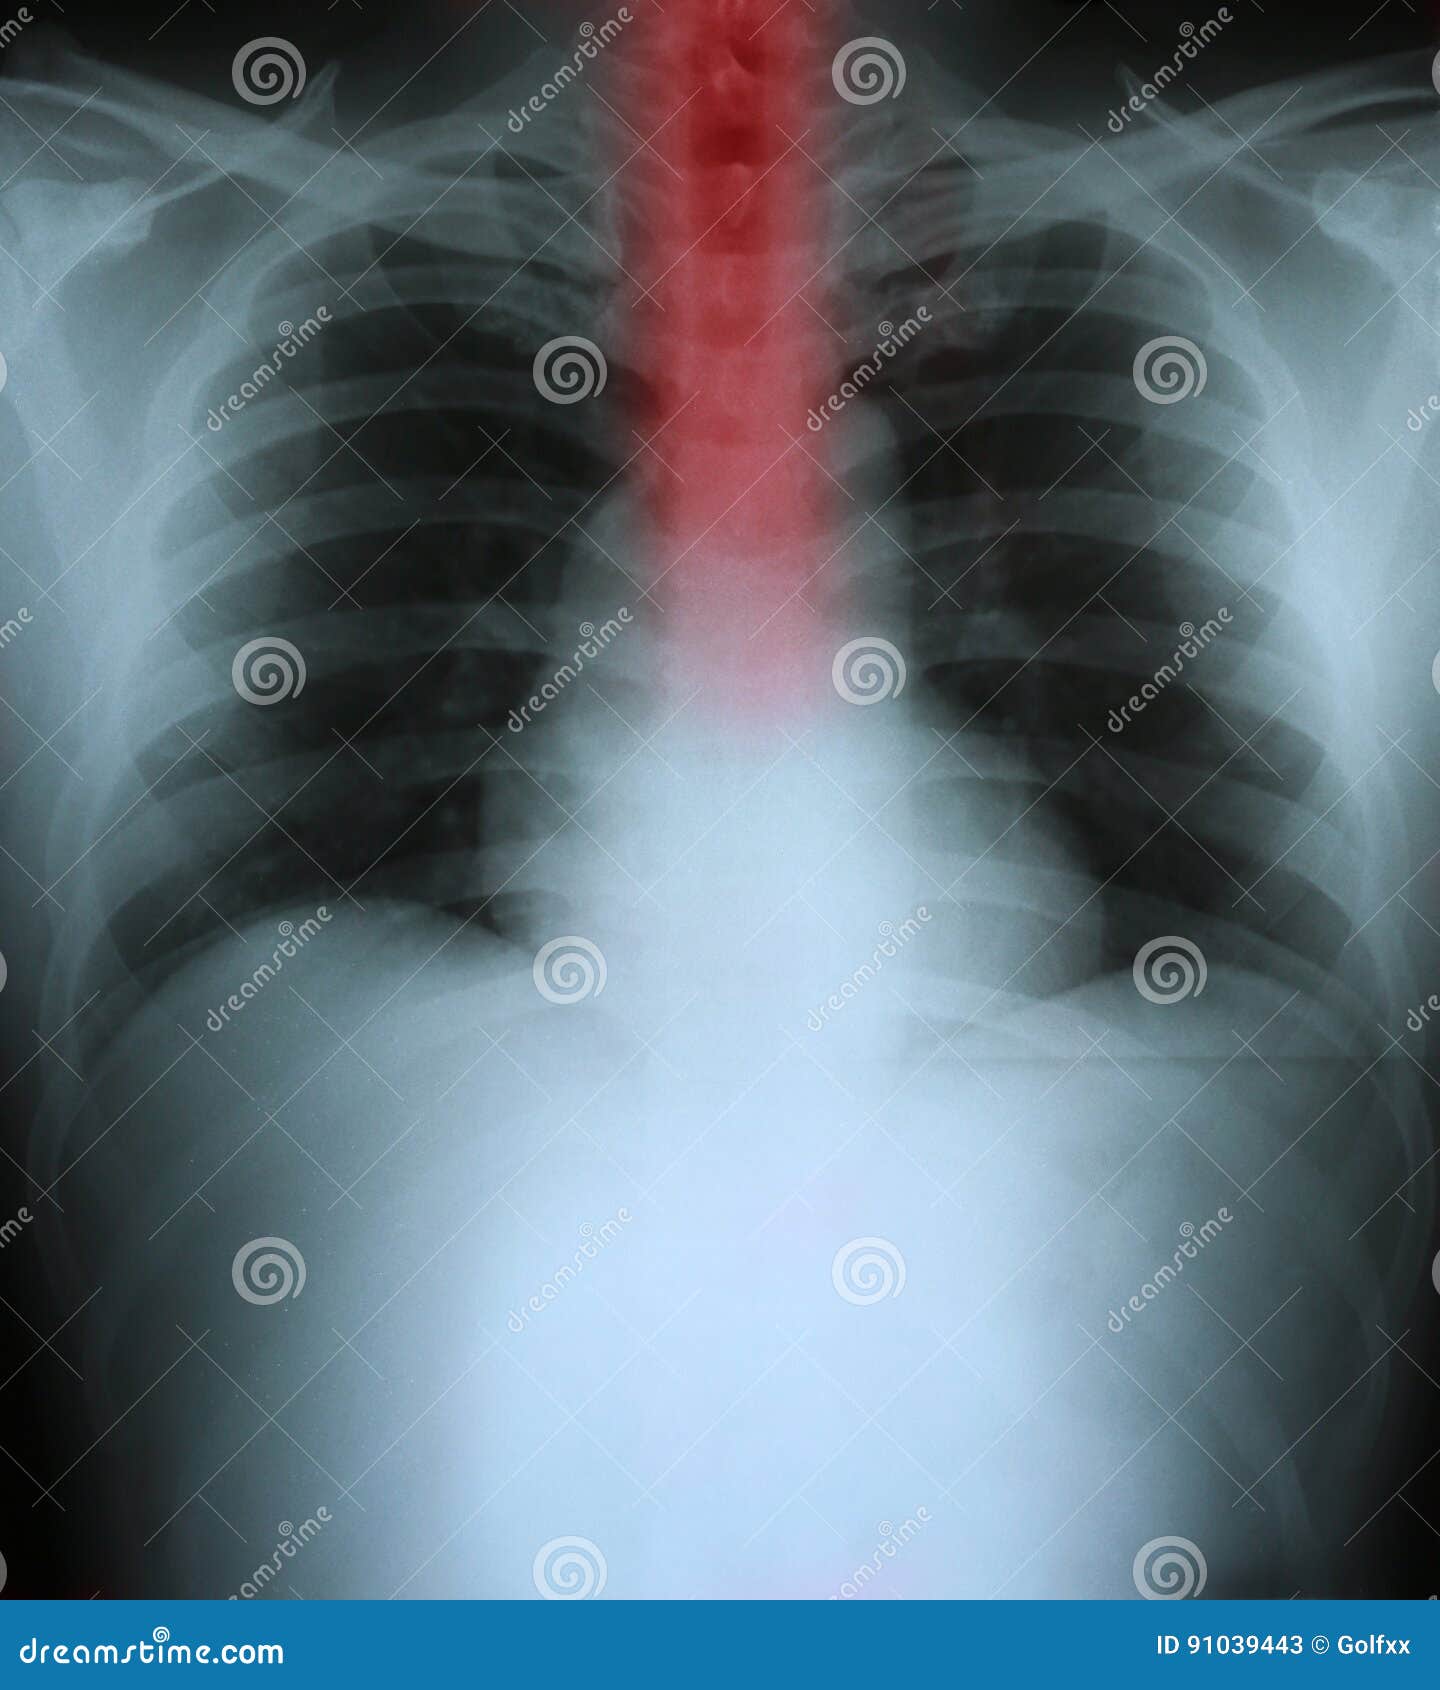

From www.dreamstime.com

Xray of a Human Thorax with Esophagus Highlighted Stock Image Image Does Chest X-Ray Show Esophagus If your doctor thinks you might have esophageal cancer, exams, tests, and a biopsy (a sample of esophagus cells) will be needed to confirm the. For an endoscopy and expect to get the same kind of workup that you would at. It looks for any problems in your oesophagus or stomach, including oesophageal cancer. However, this test cannot provide information. Does Chest X-Ray Show Esophagus.